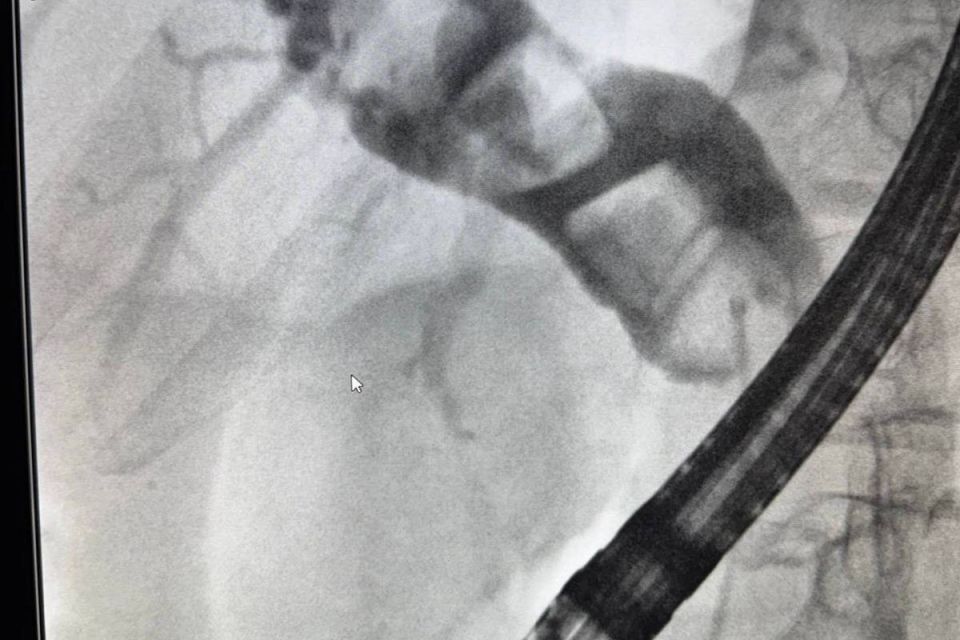

Мужчина был экстренно доставлен в тяжелом состоянии и болями. Обследование выявило, что камни перекрыли желчные протоки. Врачи успешно провели операцию по их удалению. Всего через 4 дня пациента выписали в...